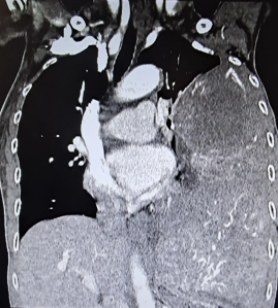

来到南方医科大学中西医结合医院时,陈阿婆左腹鼓起的大包块已越来越明显,在她消瘦的身体上显得十分突兀。通过检查发现脾脏体积异常增大,约为15cm*10cm,胃、胰腺、左肾因此受压移位,造成身体不适。

考虑到患者高龄且肿块巨大,手术创面大可能引发大出血的风险,薛琪决定采取微创手术的方法来减少患者出血。一切准备就绪后,薛琪主任为患者在全麻下进行腹腔镜探查+脾脏切除术,术中通过腹腔镜对脾脏及相关血管进行了精细解剖和分离,手术过程顺利,成功为患者切除近二十厘米的巨大肿物,几乎有一个排球那么大!

全脾切除后,测量体积为20*16*7.5cm,而正常脾脏的大小仅为10*6*3到12*8*4cm左右。术后病理诊断发现全脾大片状坏死周围见血管增生,间质较多淋巴细胞、浆细胞浸润,结合HE形态及免疫组化结果,诊断为“脾硬化性血管瘤样结节性转化”。